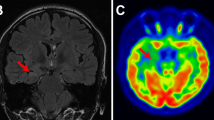

A 9-year-old male with drug-resistant epilepsy, developmental delay, and autism. a Coronal T2-weighted images show a subtle loss of gray-white matter differentiation in the right temporal lobe (arrow). b–c Coronal FDG-PET images show markedly decreased metabolic activity in the left temporal lobe, aiding in identifying this subtle malformation retrospectively seen on the initial MRI interpretation. This case illustrates the complementary role of FDG-PET and MRI in identifying the epileptogenic focus associated with subtle anatomic abnormalities